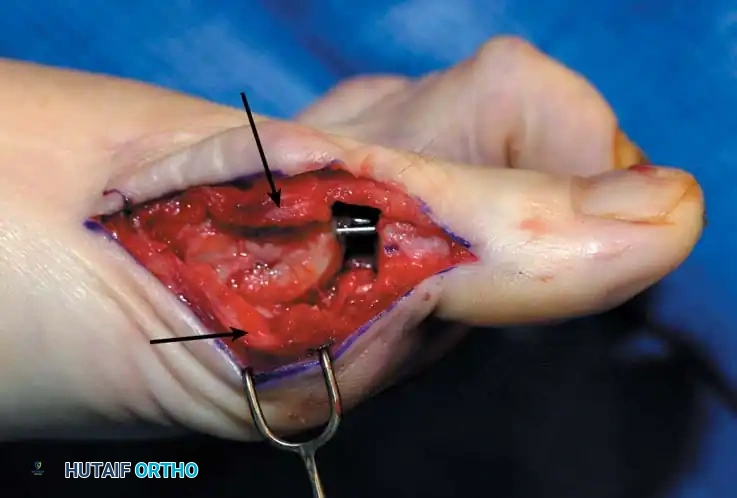

• When the sesamoid has been removed, insert two 0.062-inch Kirschner wires retrograde from the tip of the toe 2 to 3 mm plantar to the nail bed, leaving about 5 to 7 mm of the pins exposed at the base of the phalangeal remnant to help align the phalanx on the metatarsal before antegrade passage of the pins into the metatarsal (Fig. 78-31F).

Fig. 78-31 Excision of fi bular sesamoid in modifi ed Keller procedure. With base of proximal phalanx removed and medial eminence excision, exposure of fi bular sesamoid is not as diffi cult from medial incision. A, Operative photograph showing elevation of fi rst metatarsal with strong two-tooth retractor and use of small osteotome to mobilize fi bular sesamoid and lateral capsuloligamentous (frequently contracted) structures. Osteotome is between metatarsal head and lateral sesamoid. When mobilization of fi bular sesamoid is complete, entire sesamoid is visible for excision. Note chondromalacia of tibial sesamoid articular surface medial to osteotome. B, Fibular sesamoid has been excised, and lateral capsular structures and conjoined tendon (in forceps) have been released. Neurovascular bundle to lateral side of hallux is adjacent to these structures. C, Diagrammatic representation of modifi ed Keller procedure. By excising fi bular sesamoid, valgus moment of conjoined tendon of fl exor hallucis brevis and adductor hallucis no longer pulls fl exor hallucis longus tendon laterally (carrying hallux with it) through capsulosesamoid plantar plate and pulley system. D, Metatarsal head must be lifted dorsally to excise fi bular sesamoid under direct vision. E, Note exposure of fi bular sesamoid after mobilization of metatarsal head. Continued

F G

Fig. 78-31, cont’d F, Two 0.062-inch Kirschner wires are drilled distally. G, First metatarsal head is manually displaced laterally, and hallux is placed end-on the fi rst metatarsal. Kirschner wires are drilled proximally across joint. H, Capsule is mobilized dorsally and plantarward. I, 2-0 or 3-0 absorbable sutures placed in purse-string fashion are used for capsular closure. J, Capsule must be closed over joint. Note pins cut off at skin level; they also can be bent at skin level.